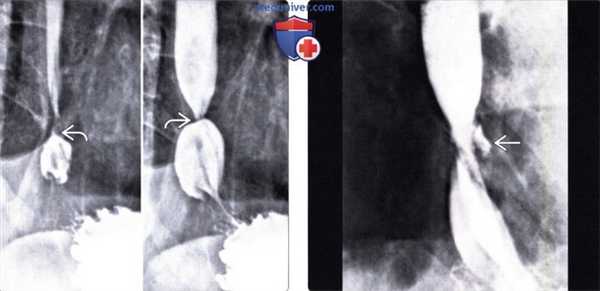

(Слева) На рисунке показаны таблетки, которые не смогли пройти по пищеводу и остановились на уровне аортального сужения. Проиллюстрирован спазм прилежащих отделов пищевода, а также язвы.

(Справа) На рентгенограмме пищевода определяется широкая, неглубокая язва на уровне дуги аорты. У пациента имелись жалобы на боль во время глотания; недавно он принимал внутрь тетрациклин. Через некоторое время симптомы самопроизвольно исчезли. Физиологические сужения пищевода, расположенные на уровне дуги аорты и ретрокардиально, чаще всего поражаются при контакте с лекарственными препаратами. (Слева) На рентгенограмме пищевода, полученной в ходе рентгеноскопии с двойным контрастированием у женщины 50 лет с жалобами на боль при глотании при приеме тетрациклина, визуализируются множественные язвы и умеренно выраженная стриктура (или спазм) дистального отдела пищевода.

(Справа) Краткий анамнез: женщина 70 лет, страдающая заболеванием сердца, проснулась от сильной боли, связанной с глотанием; накануне перед сном она принимала хинидин. На рентгенограмме пищевода с бариевой взвесью определяется протяженная стриктура (либо спазм мышечной оболочки на ограниченном участке) от верхней апертуры грудной клетки до уровня дуги аорты. Явных язв не определяется.